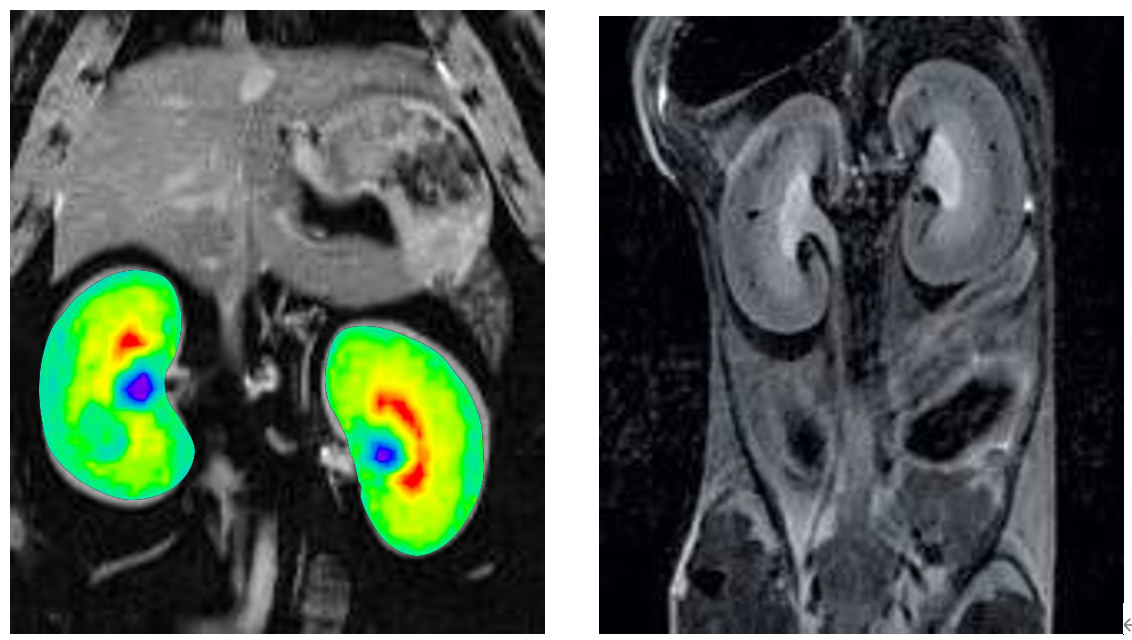

6、腹部成像

布魯克同步觸發(fā)采集技術(shù)可以消除腹部運(yùn)動(dòng)偽影,高場(chǎng)下T2對(duì)比度能更好顯示腹部各個(gè)臟器。

大小鼠腹部成像: